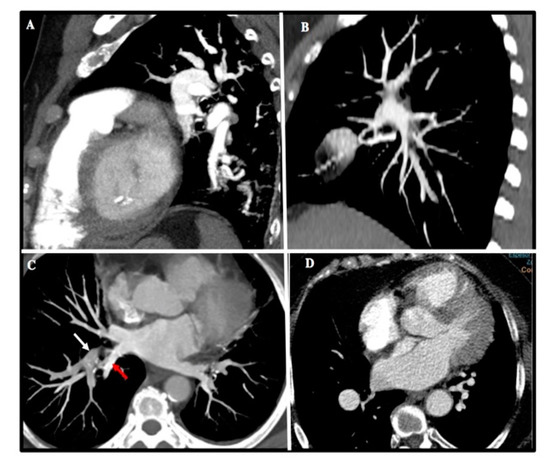

Amidst those patients who underwent PEA (n = 91), 18.7% had level I disease (Figure 5A), 45.1% level II disease, and 36.3% level III disease (Figure 5B). Table 1 summarizes the proportion of intervened patients for whom the surgical decision was based on MCTA compared with those who needed a complementary PA regarding intraoperative CTEPH classification. In up to 54% of intervened patients with level III disease, a decision on operability had been made exclusively on MCTA.

Figure 5.

Patient with proximal CTEPH (A). (a,b) Rectified interventricular septum (red thin arrow) and reduction of venous return (*). (c–e) Thromboembolic disease affecting the main pulmonary artery (red thick arrow) with extension to the right upper lobar artery (arrowhead). (f) Surgical specimen showing level I disease. Patient with distal CTEPH (B). (a–f) Organized intravascular material (thin red arrows) is identified at distal-segmental/subsegmental levels in all the pulmonary lobes. (g) Surgical specimen showing level III disease.